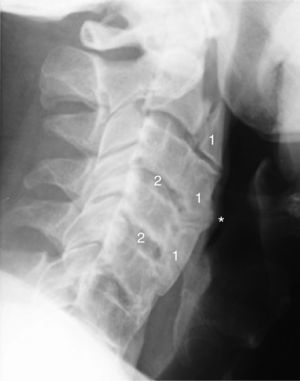

Tras valorar su evolución radiológica cervical en los últimos 5 años, de este paciente, se observa un aumento de las dimensiones de los osteofitos y de la osificación del ligamento cervical anterior afectando a varias vértebras contiguas (figs. 1 y 2), lo que podría explicar una causa extrínseca de la disfagia. También cabe destacar otras características radiológicas como son la preservación relativa del espacio intervertebral y la ausencia de afectación de las articulaciones apofisiarias.

Radiografía cervical lateral (2014). Se aprecia un aumento del tamaño de la osificación del ligamento anterior cervical con afectación global de la columna cervical (1) se puede observar como impronta (*) hacia la vía aérea-digestiva. También se observa una conservación relativa de la altura del espacio intervertebral (2).